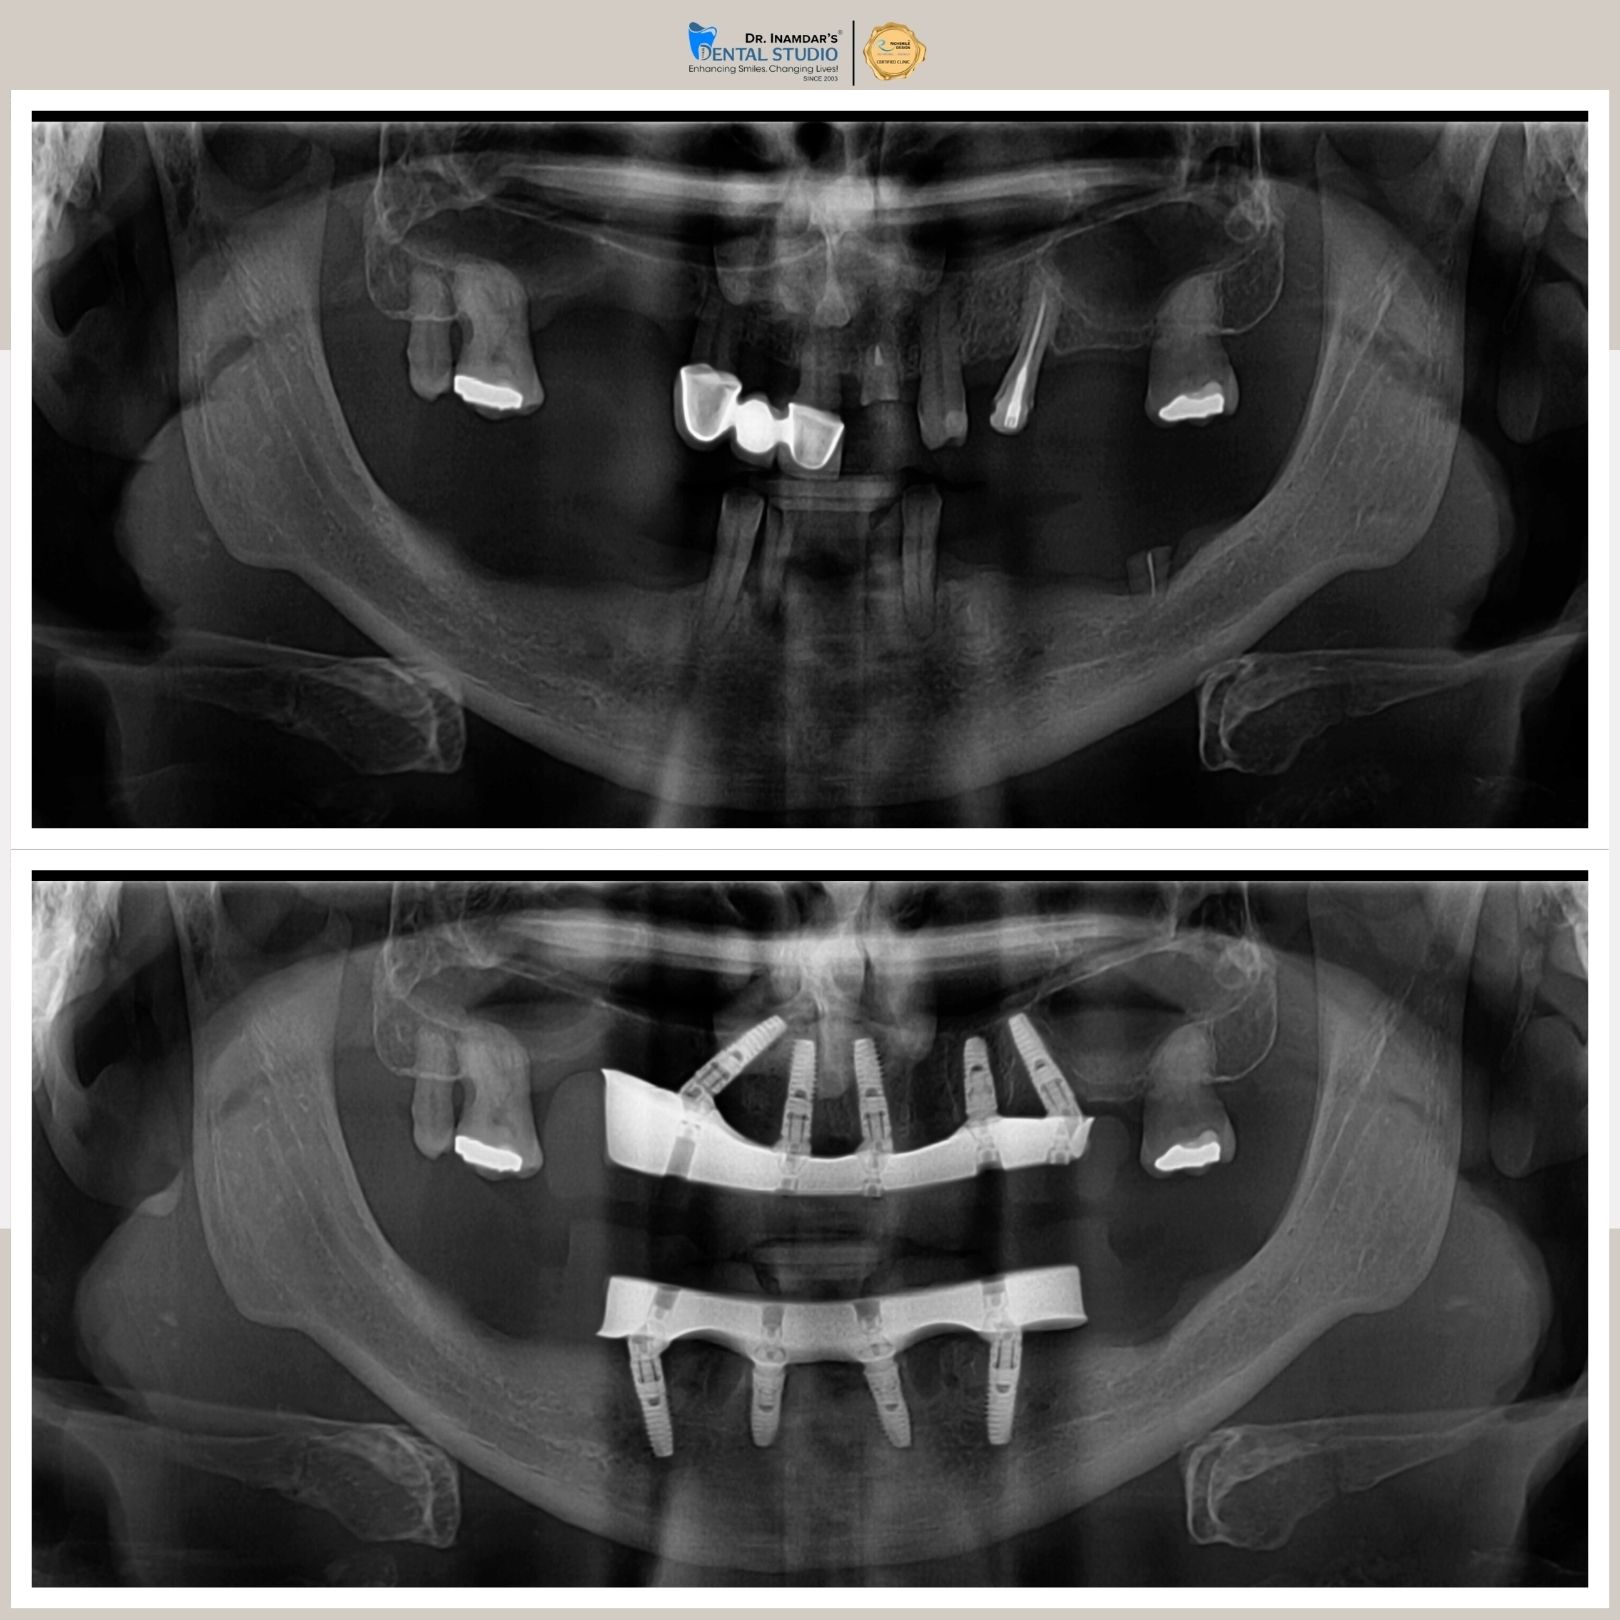

Full mouth dental implants are used to replace all missing teeth in the upper or lower jaw. A series of titanium implants are placed securely in the jawbone, and custom-made ceramic or zirconia crowns, are attached, restoring a full set of functional, natural-looking teeth.

The dental implant procedure typically involves placing the implant into the jawbone, followed by a healing period before attaching the crown.